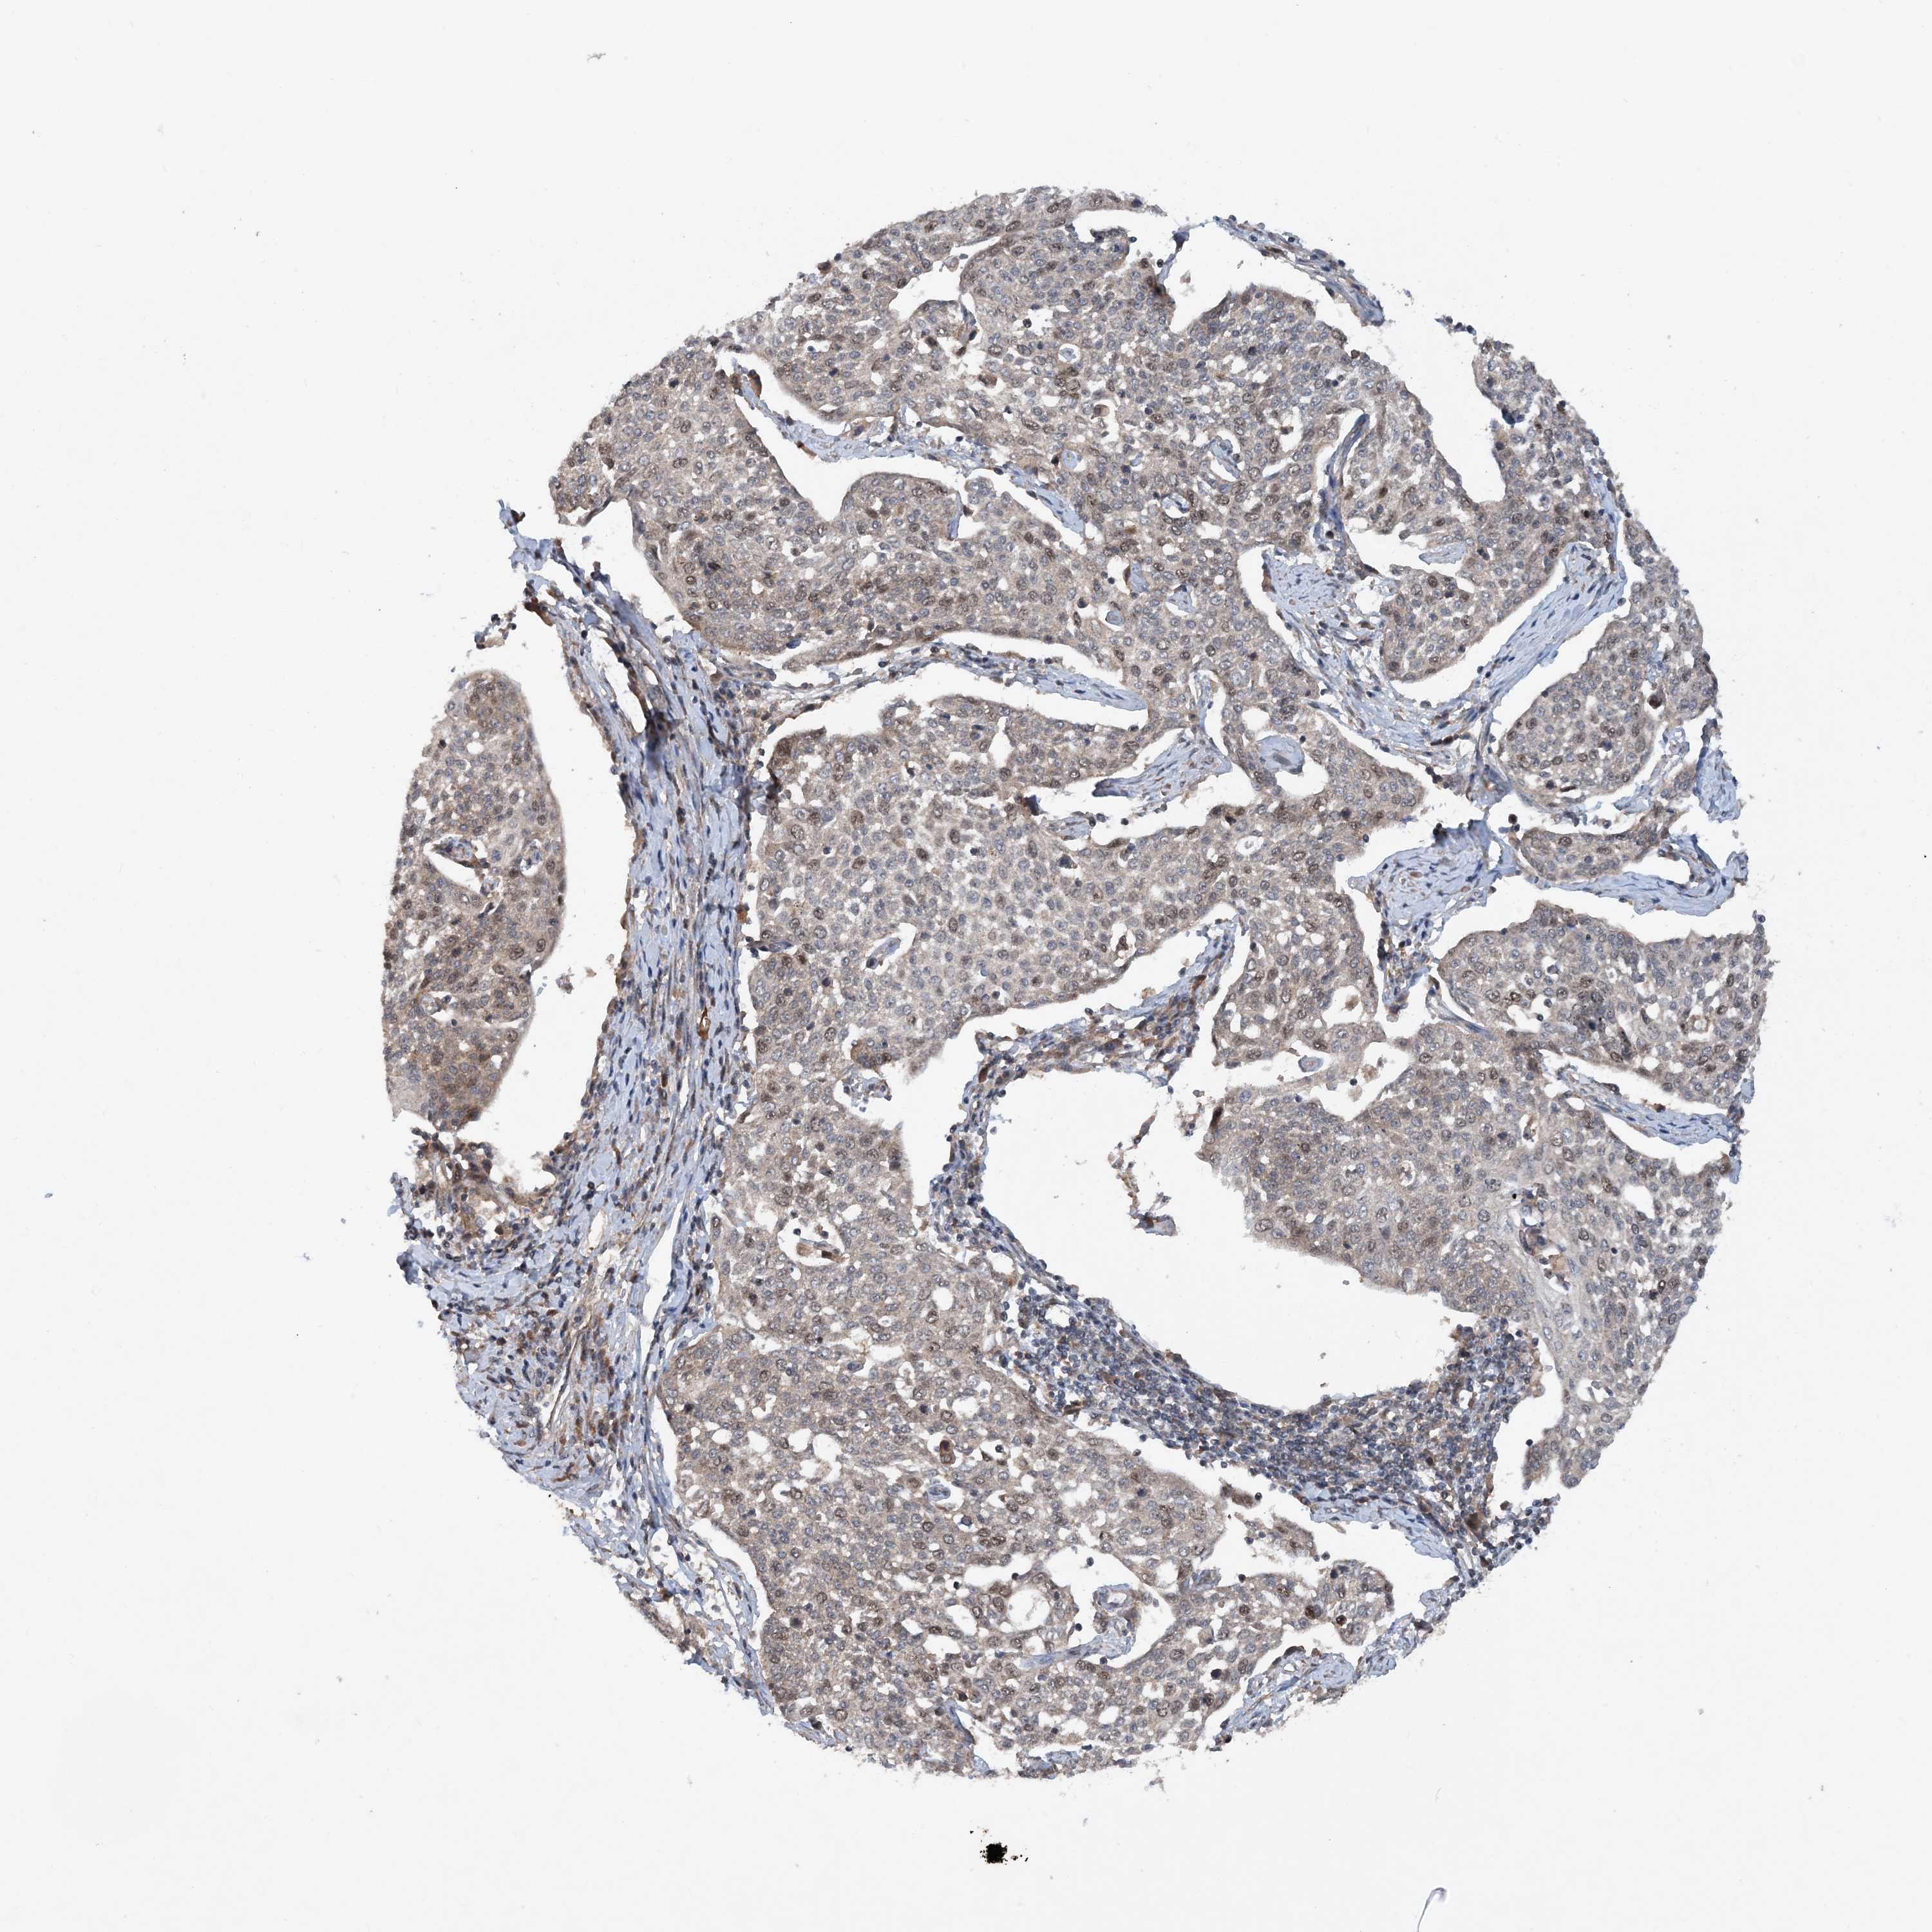

CERVICAL CANCER - Protein expressioni

A mouse-over function shows sample information and annotation data. Click on an image to view it in a full screen mode. Samples can be filtered based on level of antibody staining by selecting one or several of the following categories: high, medium, low and not detected. The assay and annotation is described here.

Note that samples used for immunohistochemistry by the Human Protein Atlas do not correspond to samples in the TCGA dataset.

Antibody stainingi

Antibody staining in the annotated cell types in the current human tissue is reported as not detected, low, medium, or high, based on conventional immunohistochemistry profiling in selected tissues. This score is based on the combination of the staining intensity and fraction of stained cells.

Each image is clickable and will lead to virtual microscopy that enables deeper exploration of all samples and also displays staining intensity scores, fraction scores and subcellular localization as well as patient and tissue information for each sample.

Antibody HPA034701

Antibody HPA034702

Staining

High

Medium

Low

Not detected

Intensity

Strong

Moderate

Weak

Negative

Quantity

>75%

75%-25%

<25%

None

Location

Nuclear

Cytoplasmic/membranous

Cytoplasmic/membranous,nuclear

Squamous cell carcinoma, NOS

Adenocarcinoma, NOS